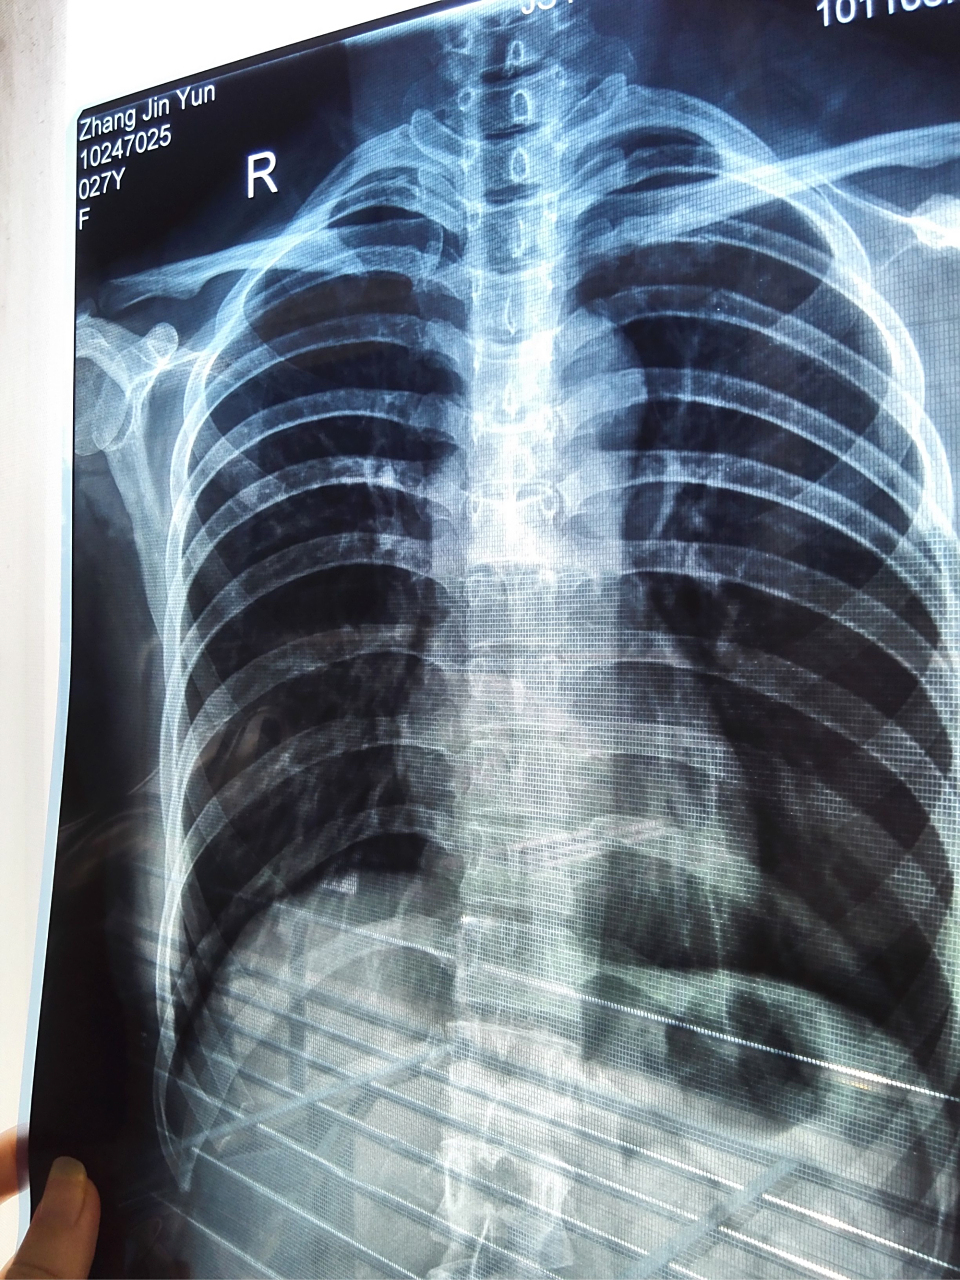

株洲男子暴力对待女友,致其骨折,网友:处罚太轻了,必须严惩!

患者胸痛,行胸部ct检查,发现右肺 - 抖音